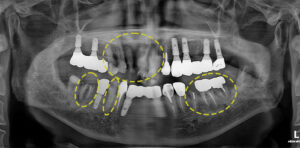

위 환자분은 다수의 치아가 흔들리고

부러져 전체적인 치료를 진행하고자

본 원에 내원해 주셨는데요.

사진을 보시면 앞니에는 부분적으로

파절되어 있음은 물론, 염증도 발생한 상태였고

오른쪽 아래 어금니들도 과거 신경치료를 해둔 치아가

파절되고 염증도 생겨 흔들림이 있었어요. 😥

반대쪽도 좋지 못한건 마찬가지 였는데요..

큰 어금니는 신경치료가 되어 있었지만 부러져 있고,

작은 어금니는 충치로 인해 치아가

부분적으로 파절된 상태였어요.

결과적으로 임플란트를 제외한

거의 모든 치아는 치료가 필요한 상태였어요.